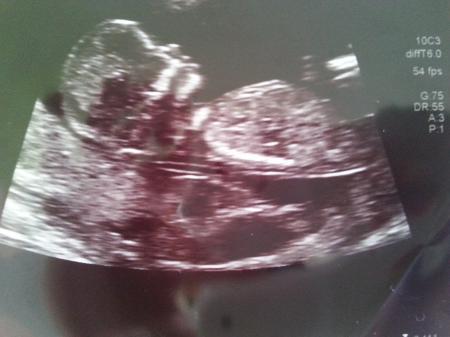

Er hat alles an dem Baby untersucht, es ist alles dran und alles drin und es wird zu 80% ein Mädchen

Die nackenfalte total unauffällig und Nasenbein ist auch vorhanden #

Man konnte alle Finger und die Füßchen sehen und im Profil soooo süß

Hier meine Maus

Süüüüüüßßßßßßßßßßß

Wow sooo ein schönes Bild - wahnsinns Profil